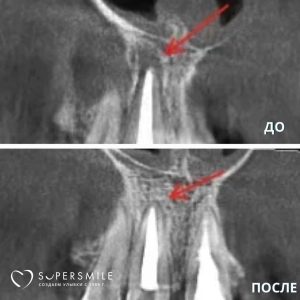

Работы наших специалистов по лечению каналов зуба